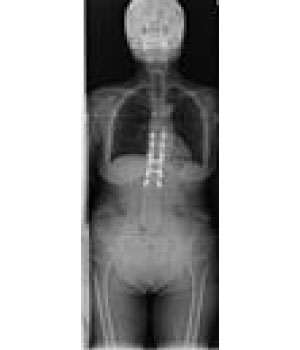

エックス線を利用して検査をするいわゆる“レントゲン撮影”です。

胸部、腹部、全身の骨の撮影を行います。心臓の大きさや肺の異常陰影、ガスの状態や骨の形、骨折の有無、関節の状態などがわかります。

当院ではフラットパネル(FPD)というシステムを導入し従来よりもエックス線の感度が高く低被ばくで撮影ができるようになりました。撮影効率も向上し撮影待ち時間も短縮しています。